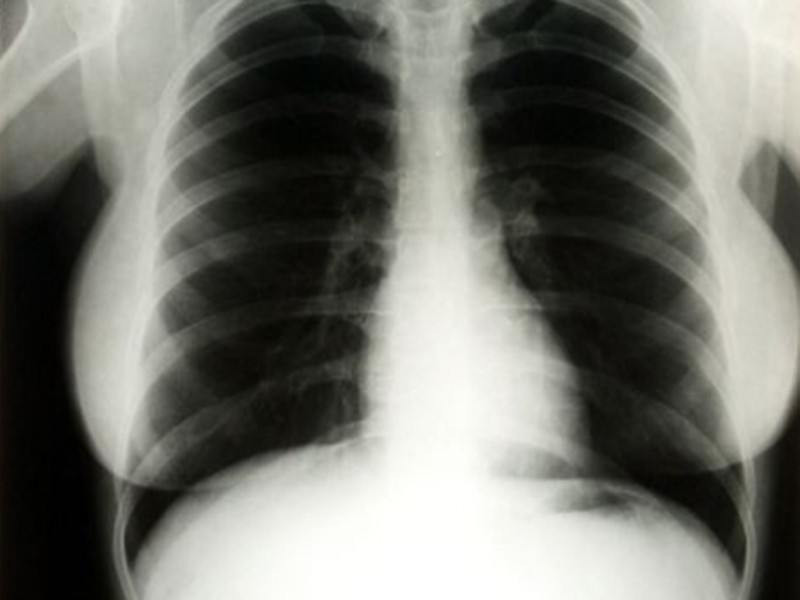

Выставка с флюорографическими снимками известных горожан открылась в Вологде

Фото:thenews.kz

Выставка «Твой главный снимок» открылась 25 марта в Вологде. На экспозиции представлены флюорографические снимки известных горожан. Выставка посвящена Всемирному дню борьбы с туберкулезом, который отмечают 24 марта.

Как сообщает ИА «СеверИнформ», снимки своих лёгких сделали вологодские политики, общественные и культурные деятели, а также журналисты. Кроме того, каждый, кто захочет обследоваться без направления, сможет также сделать флюорографию в передвижном аппарате. Он будет работать рядом с торговым центром в течение нескольких дней после открытия выставки в торгово-развлекательном центре на Окружном шоссе, 13.

Добавим, по информации сайта областного Департамента здравоохранения, сейчас зарегистрировано 905 вологжан, зараженных туберкулезом. Но можно сказать, что общий показатель заболеваемости и смертности по этой причине в регионе за последние пять лет снизился. Медики связывают это с профилактическими мероприятиями, направленными на борьбу с этим заболеванием.